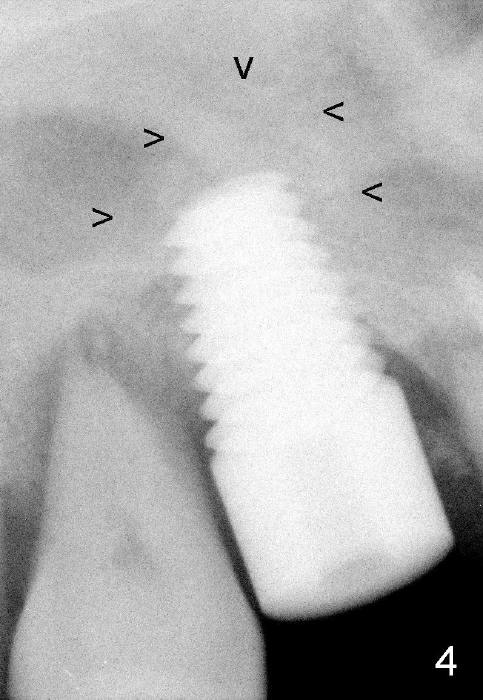

The 60-year-old man is a bruxer. All of the three upper right molars are nonsalvageable (Fig.1). Since #2 is symptomatic, it is planned to be extracted and restored first. As expected, there is severe alveolar destruction (single large socket), while the base bone is solid. A series of tapered osteotomes (2-5 mm) are used to create osteotomy in the base bone (gaining 4 mm into new bone), followed by 4.5x20 mm tap at the depth of 17 mm from the gingival margin (Fig.2). Then the depth is adjusted to 14 mm; the bone expansion and osteotomy continue until using 7 mm tap with good binding to the bone (Fig.3). A 7x14 mm implant is placed with insertion torque more than 60 Ncm (Fig.4). No bone graft is used for sinus lift considering sinus membrane perforation. The buccal flap is raised to reveal bony defect, which is covered by Osteogen (a synthetic bone graft) and then collagen membrane (Fig.6 *). Five days postop, the membrane undergoes a type of transformation (Fig.7 *) leading to a gingival tissue (Fig.8 *, 18 days postop). By 3 months, the gingiva has normal appearance (Fig.9), while the implant seems to be osteointegrated (Fig.10). Once the infected source is removed, our body has potential to regenerate.

The patient complains food impaction between #1 and 2, six months post cementation. The former has mobility II. Although there is keratinized gingiva buccal to these sites (Fig.12), there is no papilla buccally (Fig.13) or palatally (Fig.14). The palatal pockets between #1 and 2 are deep with tenderness. X-ray shows bone loss between the sites (Fig.11 white *); the periodontal explorer can be felt to touch the distal implant threads (<). Extraction and immediate implant are recommended for #1. Twelve months later, the patient agrees with the treatment plan. The tooth #3 needs extraction and immediate implant, 2.5 years after the one at #2.